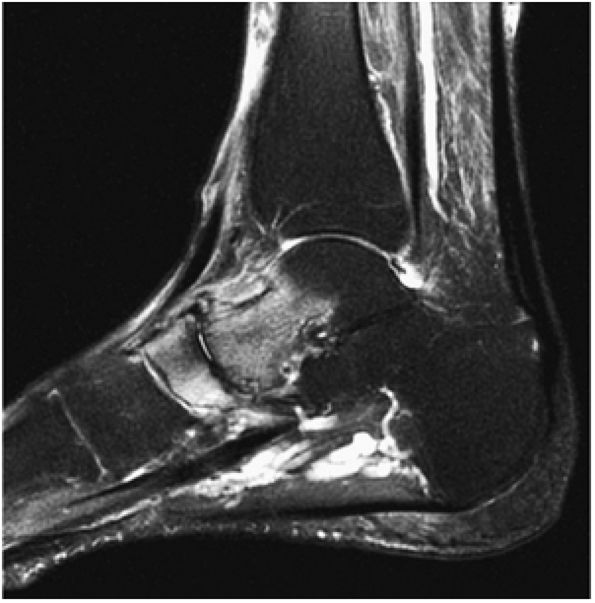

FIGURE 5.100 ● (A) Stage IV OLT with interruption of the subchondral plate, subchondral cystic change, and medially displaced chondral fragment on a coronal section color illustration. (B, C) Stage IV OLT with the displaced fragment located in the anterior tibiotalar joint capsule. The lateral OLT is the donor site. Arthroscopy is performed on all stage III and IV lesions and stage I and II lesions that fail conservative treatment. (B) Coronal T1-weighted image. (C) Axial FS PD FSE image. (D) Displaced fragment from a medial talar dome donor site in OLT on a color graphic superior view of the talus with the tibia and fibula resected.